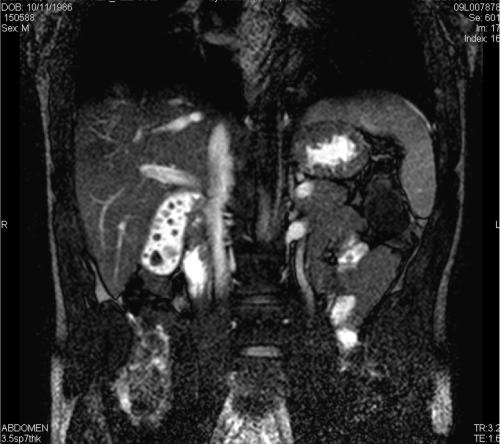

I calcoli biliari sono piccoli granuli di materia che si sviluppano nella cistifellea, la grande ghiandola che si trova a fianco del fegato che ha il compito di contenere e secernere all’occorrenza la bile per aiutare l’intestino nel processo digestivo.

Quando nella bile si presentano in alta quantità sia colesterolo che bilirubina, queste sostanze possono indurirsi formando dei granuli.